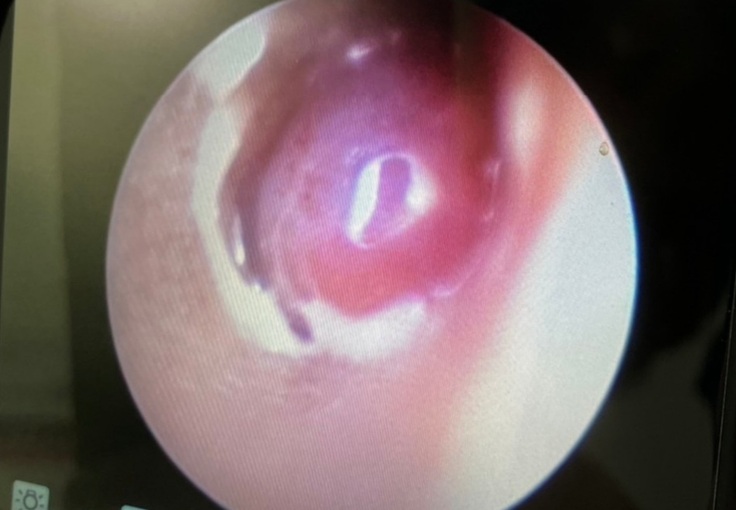

耳の中を見ると大きな出来物?が見受けられたとのことで肉腫なのか異物なのかを確認してから、焼きながら切除とのことでした。

手術の結果としては外耳に腫瘍がありそちらを少しずつ取り除いていただきました。

一枚目は手術前、2枚目は切除あと。

ただ問題は鼓膜近くの見えている外耳の腫瘍ではなく、その先。つまり鼓膜の中、中耳の鼓室から腫瘍が派生していると思われるとのこと。

鼓膜を破っての腫瘍の派生とのこと。